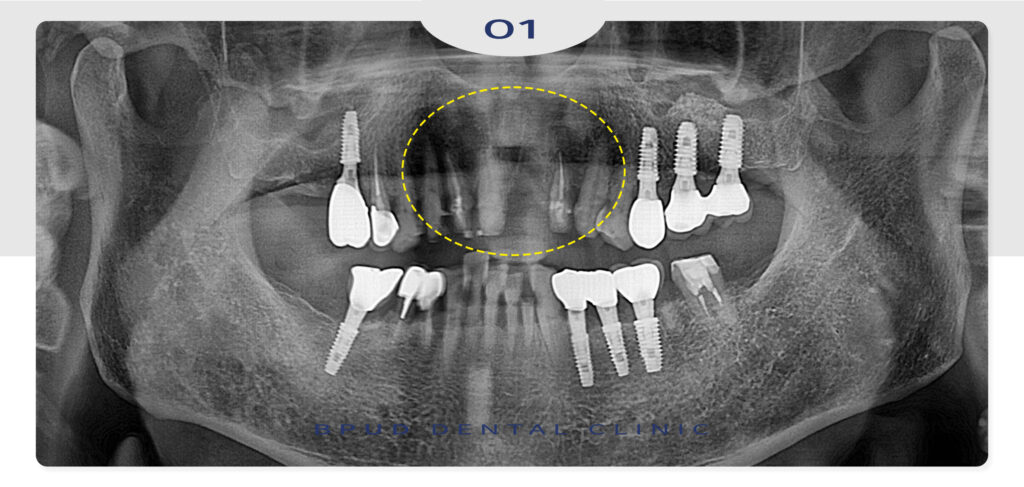

환자분께서는 기존에 부평동치과에 내원 중이셨던

환자분으로 앞니의 충치가 점점 심해져

보기 싫을 정도로 까맣게 되어 미루고 미루다

최소 비용으로 치료를 원하신다는 말씀을 해주셨는데요.

따라서 충치가 심하게 진행된 왼쪽 앞니는 발치하고

양쪽은 신경치료를 진행하기로 계획을 수립하였고

비용 문제와 빠른 치료 결과를 원하시는 환자분의

말씀을 고려하여 발치한 부위에도 따로 임플란트 식립 없이

브릿지 형태의 보철로 진행하기로 하였습니다.